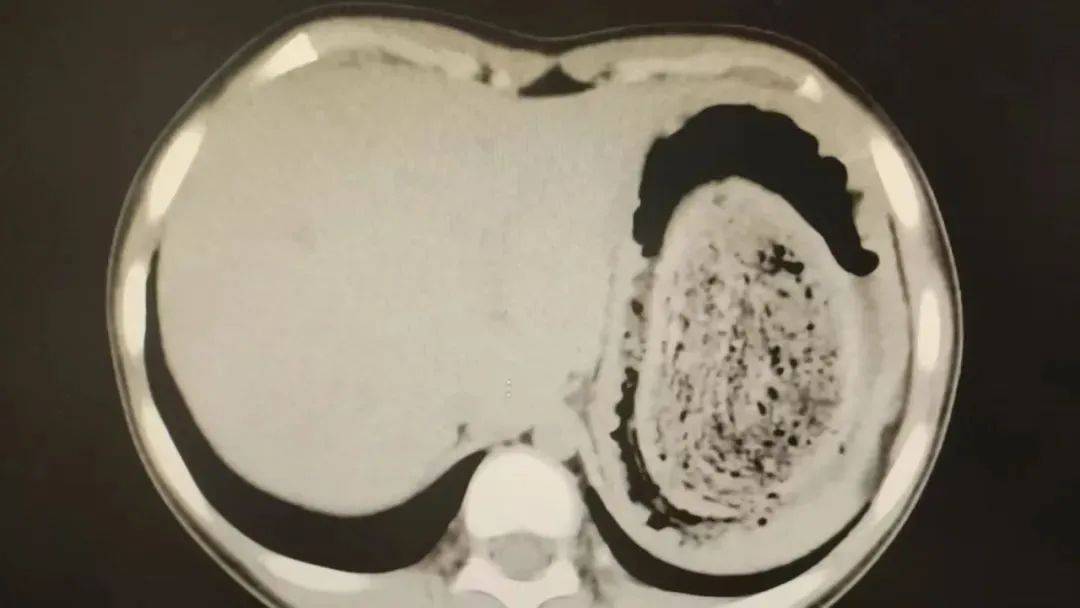

在胃镜帮助下,妮妮胃里的情况逐渐明了皇冠信用网登2。一个滚圆黑色的毛发球混合着食物残渣占据整个胃腔,这些头发相互缠绕形成一个实心的“发石”,此外胃里还有一个鸡蛋大小的溃疡。

症结找到了,就是这个巨大的发石导致妮妮出现营养不良、贫血和闭经,当务之急就是取出“发石”,给胃进行“大扫除”皇冠信用网登2。

“发石”混杂着食物残渣,就像一个黑色的小西瓜皇冠信用网登2。由于整个“发石”体积太大,为避免损伤胃壁,医生借助手术工具将“发石”切割、分解,再小心翼翼地分块取出。整场手术持续2个多小时,最终取出4斤头发碎片。

10岁女孩园园(化名)因持续3天的上腹痛伴呕吐被紧急送医皇冠信用网登2。影像学检查结果显示,她的胃部存在一个巨大的团块状阴影,初步怀疑为异物堵塞。据家长回忆,园园从1年前开始就有偷偷吃头发的习惯,但家人并未重视,直到这次症状严重才意识到问题的严重性。